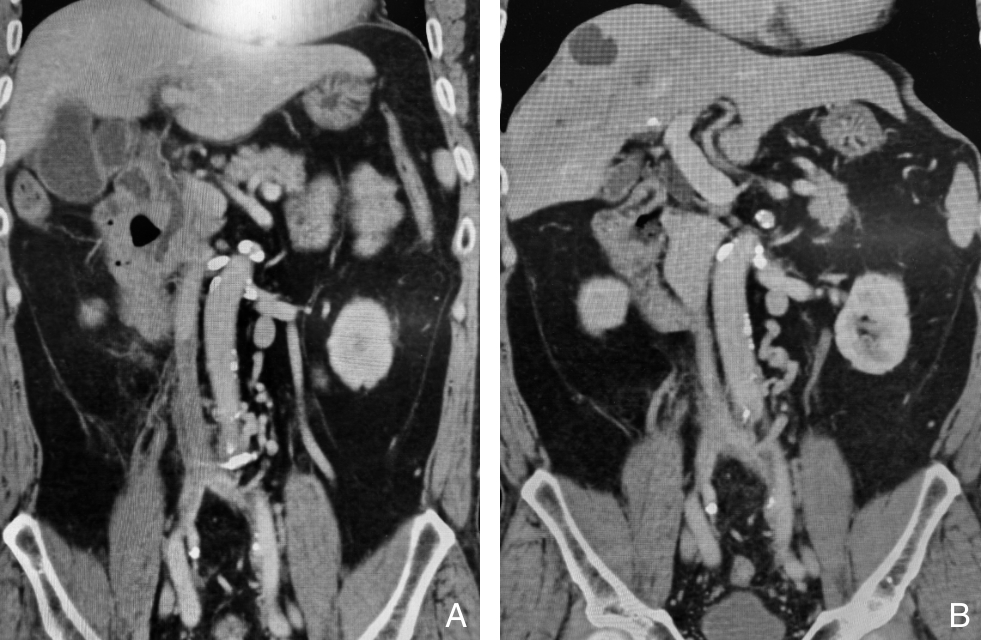

2025, 34(12):2654-2663. doi: 10.7659/j.issn.1005-6947.250621

摘要:背景与目的 慢性腔髂静脉闭塞多继发于下腔静脉滤器(IVCF)长期留置,常导致严重的血栓后综合征(PTS)。传统球囊扩张联合支架植入虽可改善短期通畅性,但中远期支架相关并发症和通畅率下降仍是临床难题。本研究旨在评估重复球囊扩张联合末次药物涂层球囊(DCB)扩张治疗慢性腔髂静脉闭塞的有效性与安全性。方法 采用单中心回顾性研究,纳入2022年1月—2024年12月接受重复球囊扩张治疗的慢性腔髂静脉闭塞患者72例,其中62例完成3次标准化球囊扩张方案并纳入分析。术后6个月行计算机断层扫描静脉造影(CTV),按下腔静脉(IVC)是否通畅分为通畅组和闭塞组。比较两组患者IVC通畅率、IVCF回收率、肢体周径、静脉疾病严重程度评分(VCSS)及Villalta评分、PTS分级及CTV影像学参数变化。结果 技术成功率为86.1%(62/72)。术后6个月IVC通畅43例(69.4%)。通畅组IVCF回收率显著高于闭塞组(100% vs. 78.9%,P=0.002)。与术前相比,通畅组膝上及膝下肢体周径显著减小,VCSS和Villalta评分明显改善,PTS严重程度显著降低(均P<0.05);CTV显示IVC中段及起始部横截面积显著增加(均P<0.05)。闭塞组上述指标均未见显著改善(均P>0.05)。围手术期未发生症状性肺栓塞、严重出血、血管破裂或死亡等严重并发症。结论 重复球囊扩张联合DCB扩张治疗慢性腔髂静脉闭塞具有良好的短期通畅效果和安全性,可显著改善临床症状及PTS严重程度,并在一定程度上避免支架植入,为慢性腔髂静脉闭塞的腔内治疗提供了一种可行策略。